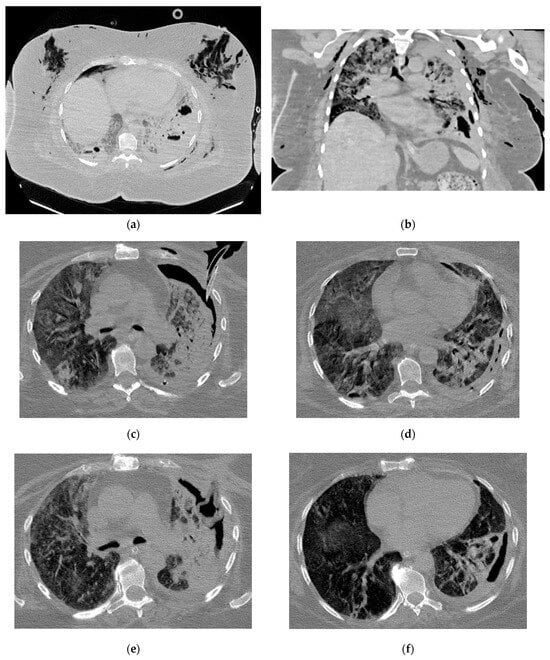

Figure 5.

Radiologic evolution of case 3: Axial chest CT scans after first percutaneous ICD insertion revealing insufficient drainage of the purulent cavity; pleural effusion with few air inclusions; right ICD and diffuse interstitial infiltrates (a,b). In this case, multiple drainage and drain revisions were necessary to optimally control the purulent infection. Smaller right residual cavity with stable pleural effusion after ICD revision (c,d). Chest CT scans 1-month follow-up show the Foley catheter and decreasing size of the residual cavity (e). A follow-up CT scan after ICD removal showed small residual pleural and pulmonary fibrotic changes (f).